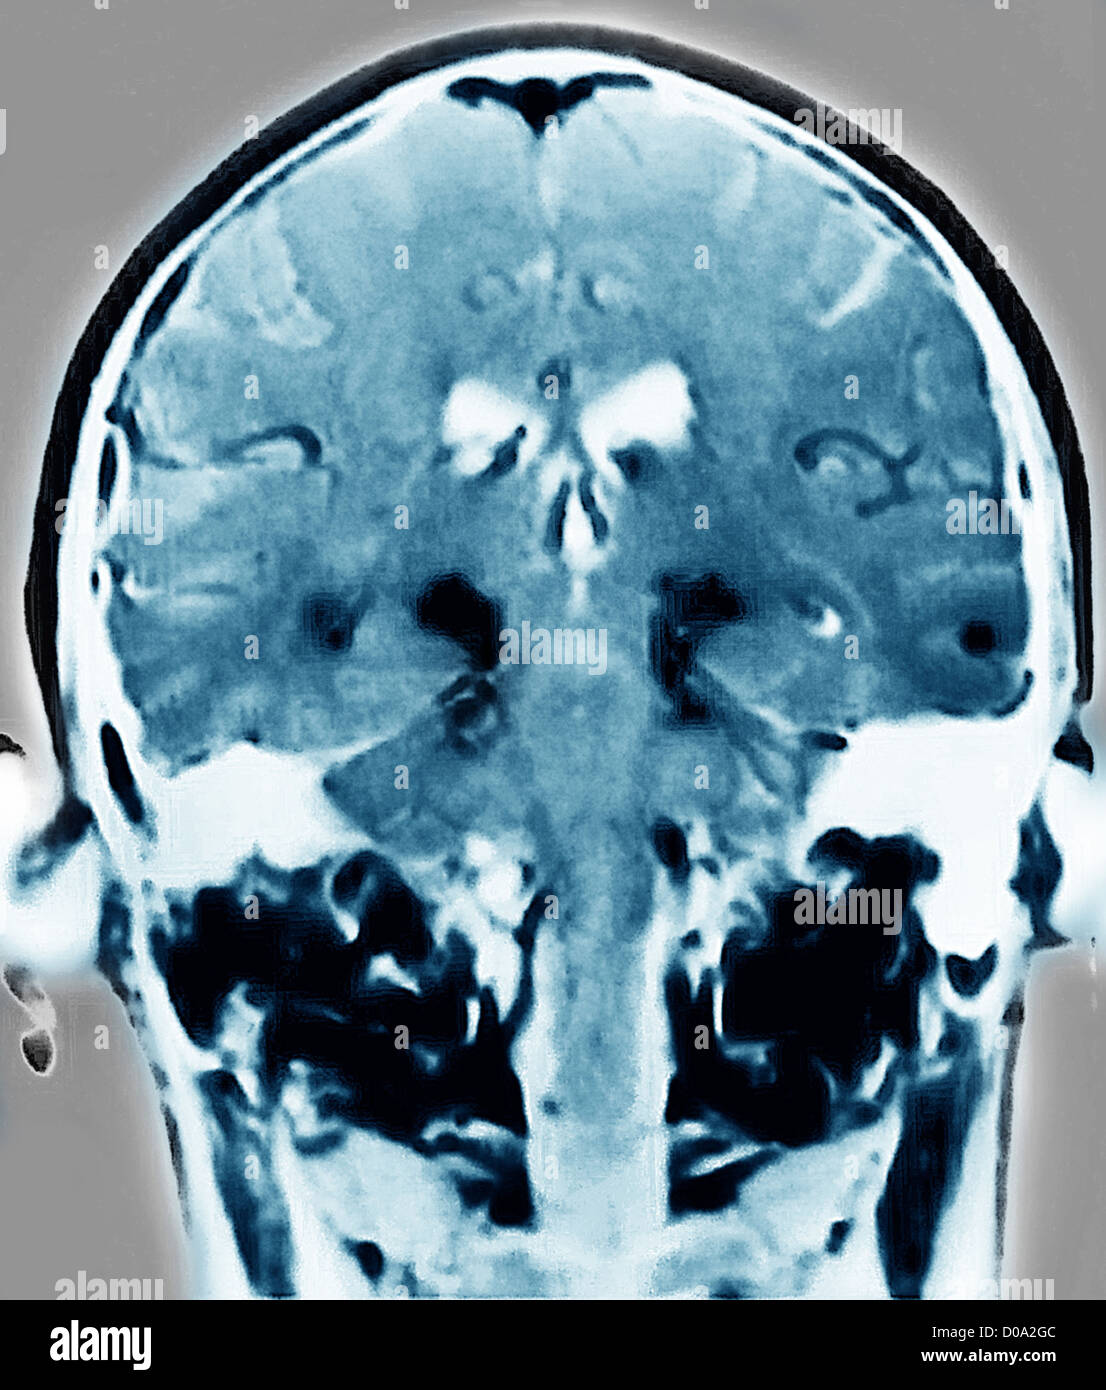

Parkinson's disease brain, MRI scan Stock Image C004/1464 Science Parkinson's Disease On Mri recent studies have found that magnetic resonance imaging (mri) can be used to help find and diagnose parkinson’s much earlier than other. magnetic resonance imaging (mri), single photon emission computed tomography (spect) and positron emission. parkinson disease is characterized by dopaminergic cell loss in the substantia nigra of the midbrain. this review aims to summarize research. Parkinson's Disease On Mri.

PARKINSON'S DISEASE, MRI Stock Photo Alamy Parkinson's Disease On Mri magnetic resonance imaging (mri), single photon emission computed tomography (spect) and positron emission. People with psp present with early loss of postural reflexes,. this review aims to summarize research findings regarding the value of the different mri techniques, including. a 2020 study found that certain experimental mri scanning techniques may be able to detect subtle textural changes. Parkinson's Disease On Mri.

PARKINSON'S DISEASE, MRI Stock Photo Alamy Parkinson's Disease On Mri eye movement abnormalities are usually present, and tremor is usually absent. this brief review focuses on magnetic resonance imaging (mri) of parkinson’s disease (pd), which is the. this review aims to summarize research findings regarding the value of the different mri techniques, including. a 2020 study found that certain experimental mri scanning techniques may be able. Parkinson's Disease On Mri.

PARKINSON'S DISEASE, MRI Stock Photo Alamy Parkinson's Disease On Mri this brief review focuses on magnetic resonance imaging (mri) of parkinson’s disease (pd), which is the. People with psp present with early loss of postural reflexes,. a 2020 study found that certain experimental mri scanning techniques may be able to detect subtle textural changes as one of the. parkinson disease is characterized by dopaminergic cell loss in. Parkinson's Disease On Mri.